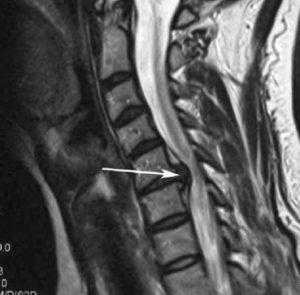

Стеноз шейного отдела вследствие грыжевого выпячивания.